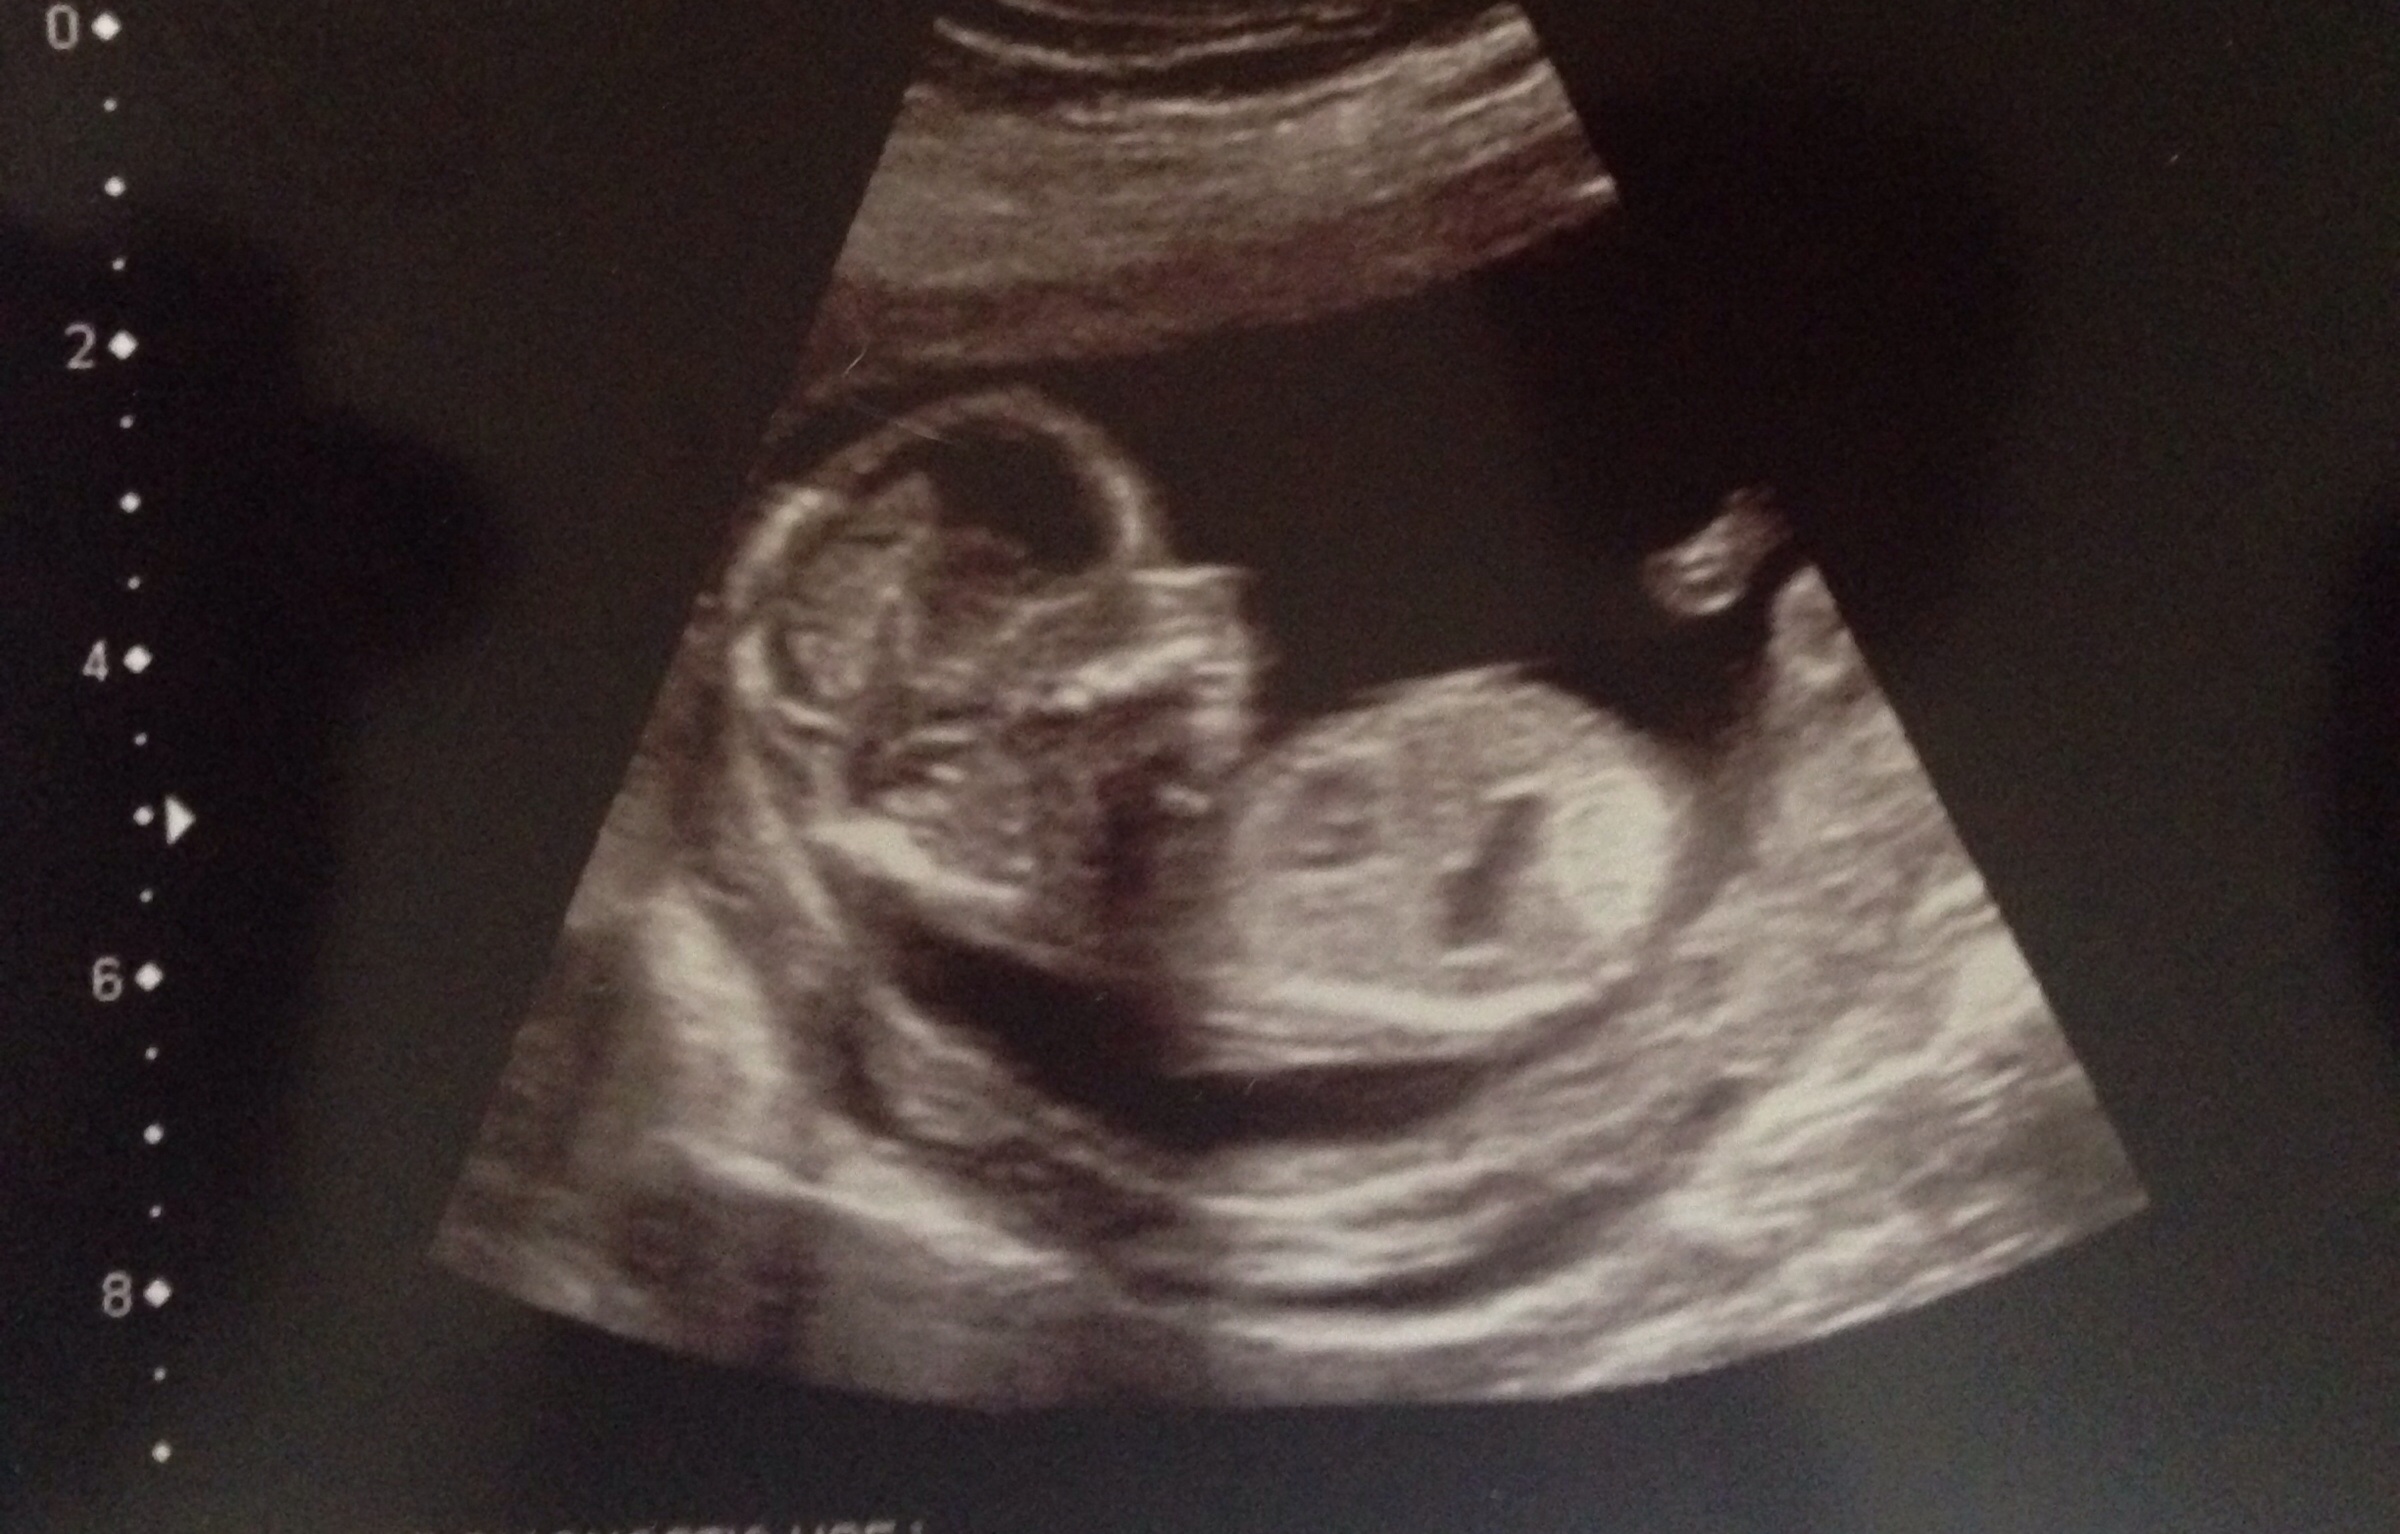

Looks like a boy

I'm as confused by your nub as much as my own! Look boy at first but then spine is curled so I'm not sure if it's horizontal to the spine which would be girl?

Guessing boy. One cute baby! Congrats!

girl!

I lean pink

Boy

I am thinking boy because there's something on top of the line, fx I'm wrong!;)

I guess girl. The nub is almost parallel to the spine and not at an angle.